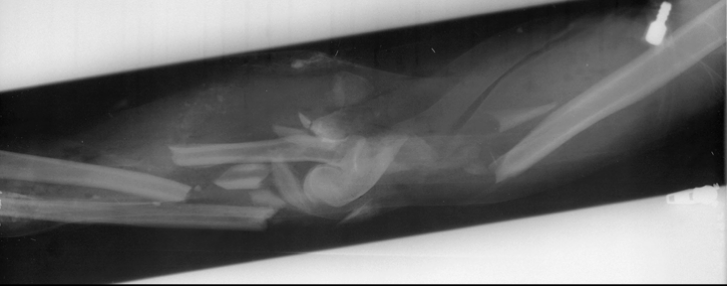

7

Q

What is the diagnosis?

What radiographic sign is present?

A

Intracapsular fracture with effusion/lipohemarthrosis

FBI sign present

8

Sail sign present